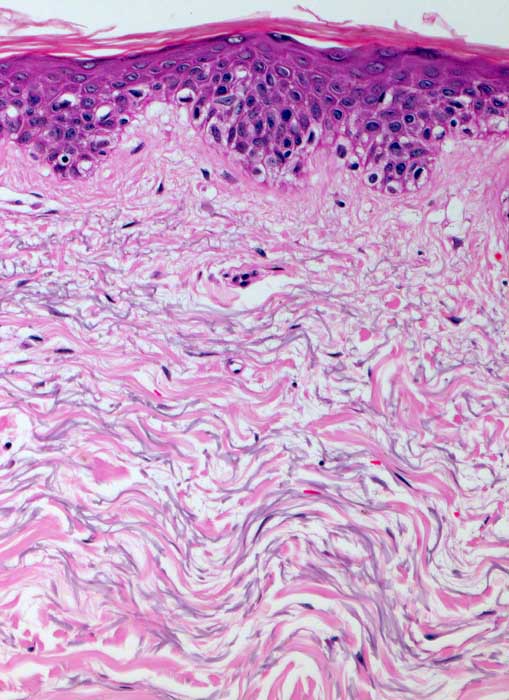

AP/ Solare Elastose

Solare Elastose

Haut

Haut, obere Extremität